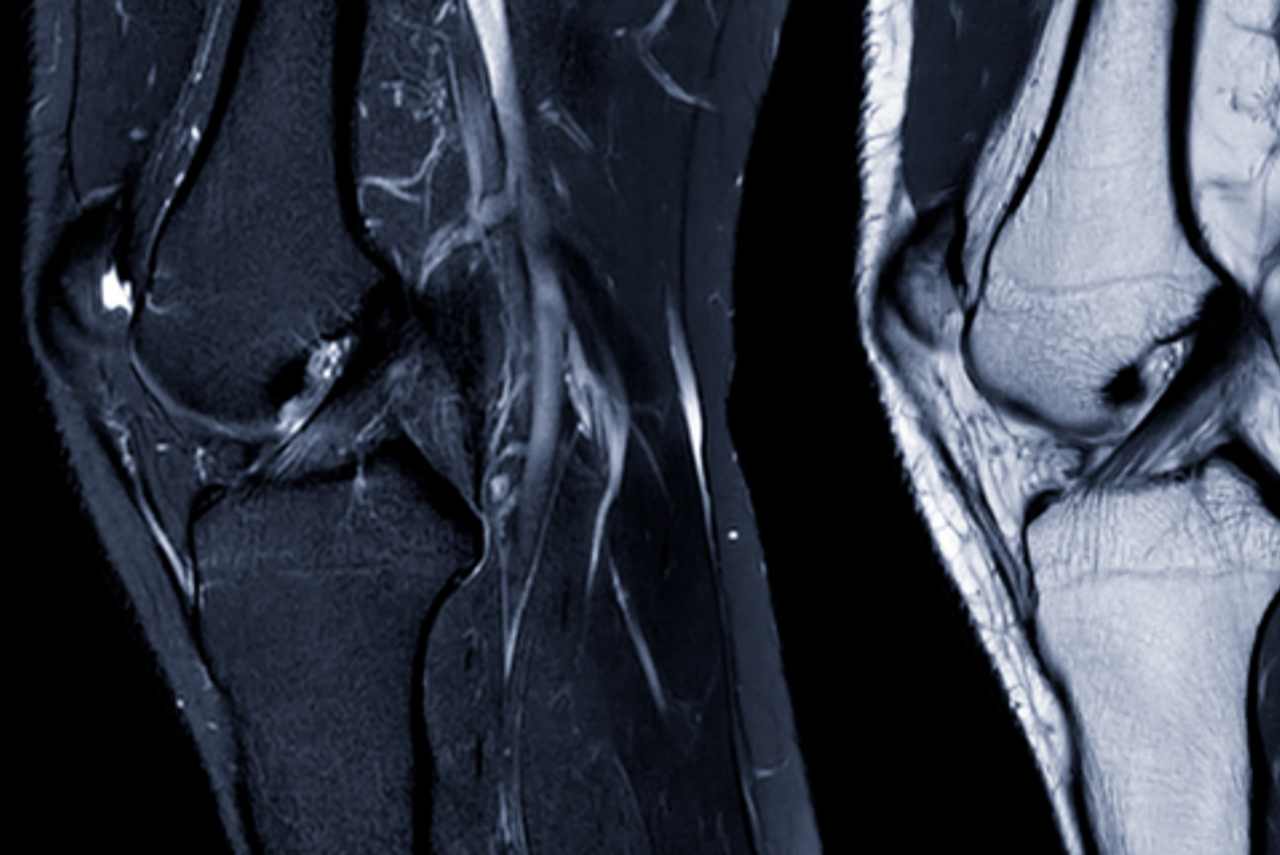

Musculoskeletal imaging can assess a wide range of medical conditions affecting the spine, shoulder, elbow, wrist, hip, knee, ankle and other joints, and helps provide high-quality images of bones, cartilage, ligaments, tendons, muscles and surrounding soft tissue structures.

A musculoskeletal MRI can help assess:

- Soft tissue injuries such as rotator cuff tears of the shoulder, tendon tears, ligament injuries or labral tears of the shoulders and hips

- Joint conditions including osteoarthritis, inflammation, effusions or reduced movement

- Referred pain or nerve-related symptoms affecting movement, strength or function

- Sports-related injuries or overuse concerns involving muscles, tendons, joints or bones

- Subtle abnormalities, bone or cartilage changes, foreign bodies or conditions that have not appeared on previous scans